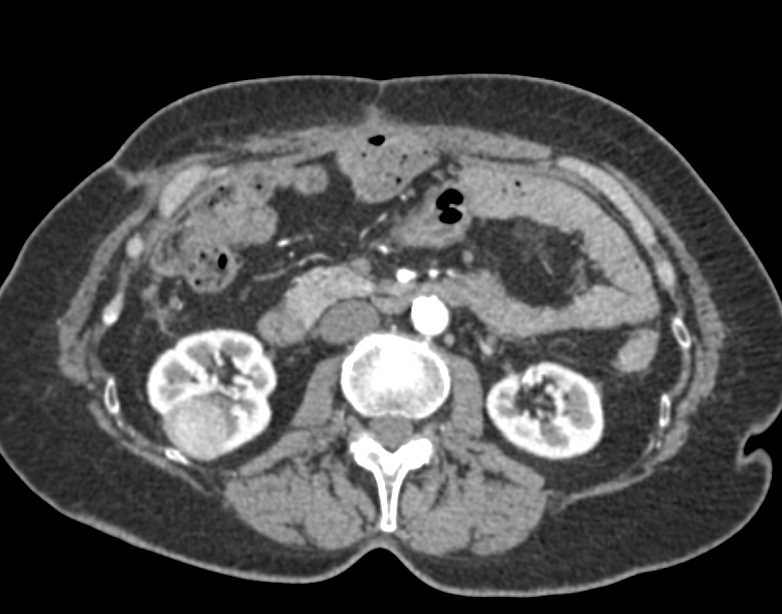

Polycystic Kidney Disease with Chronic PancreatitisCT & MRI Sumer's